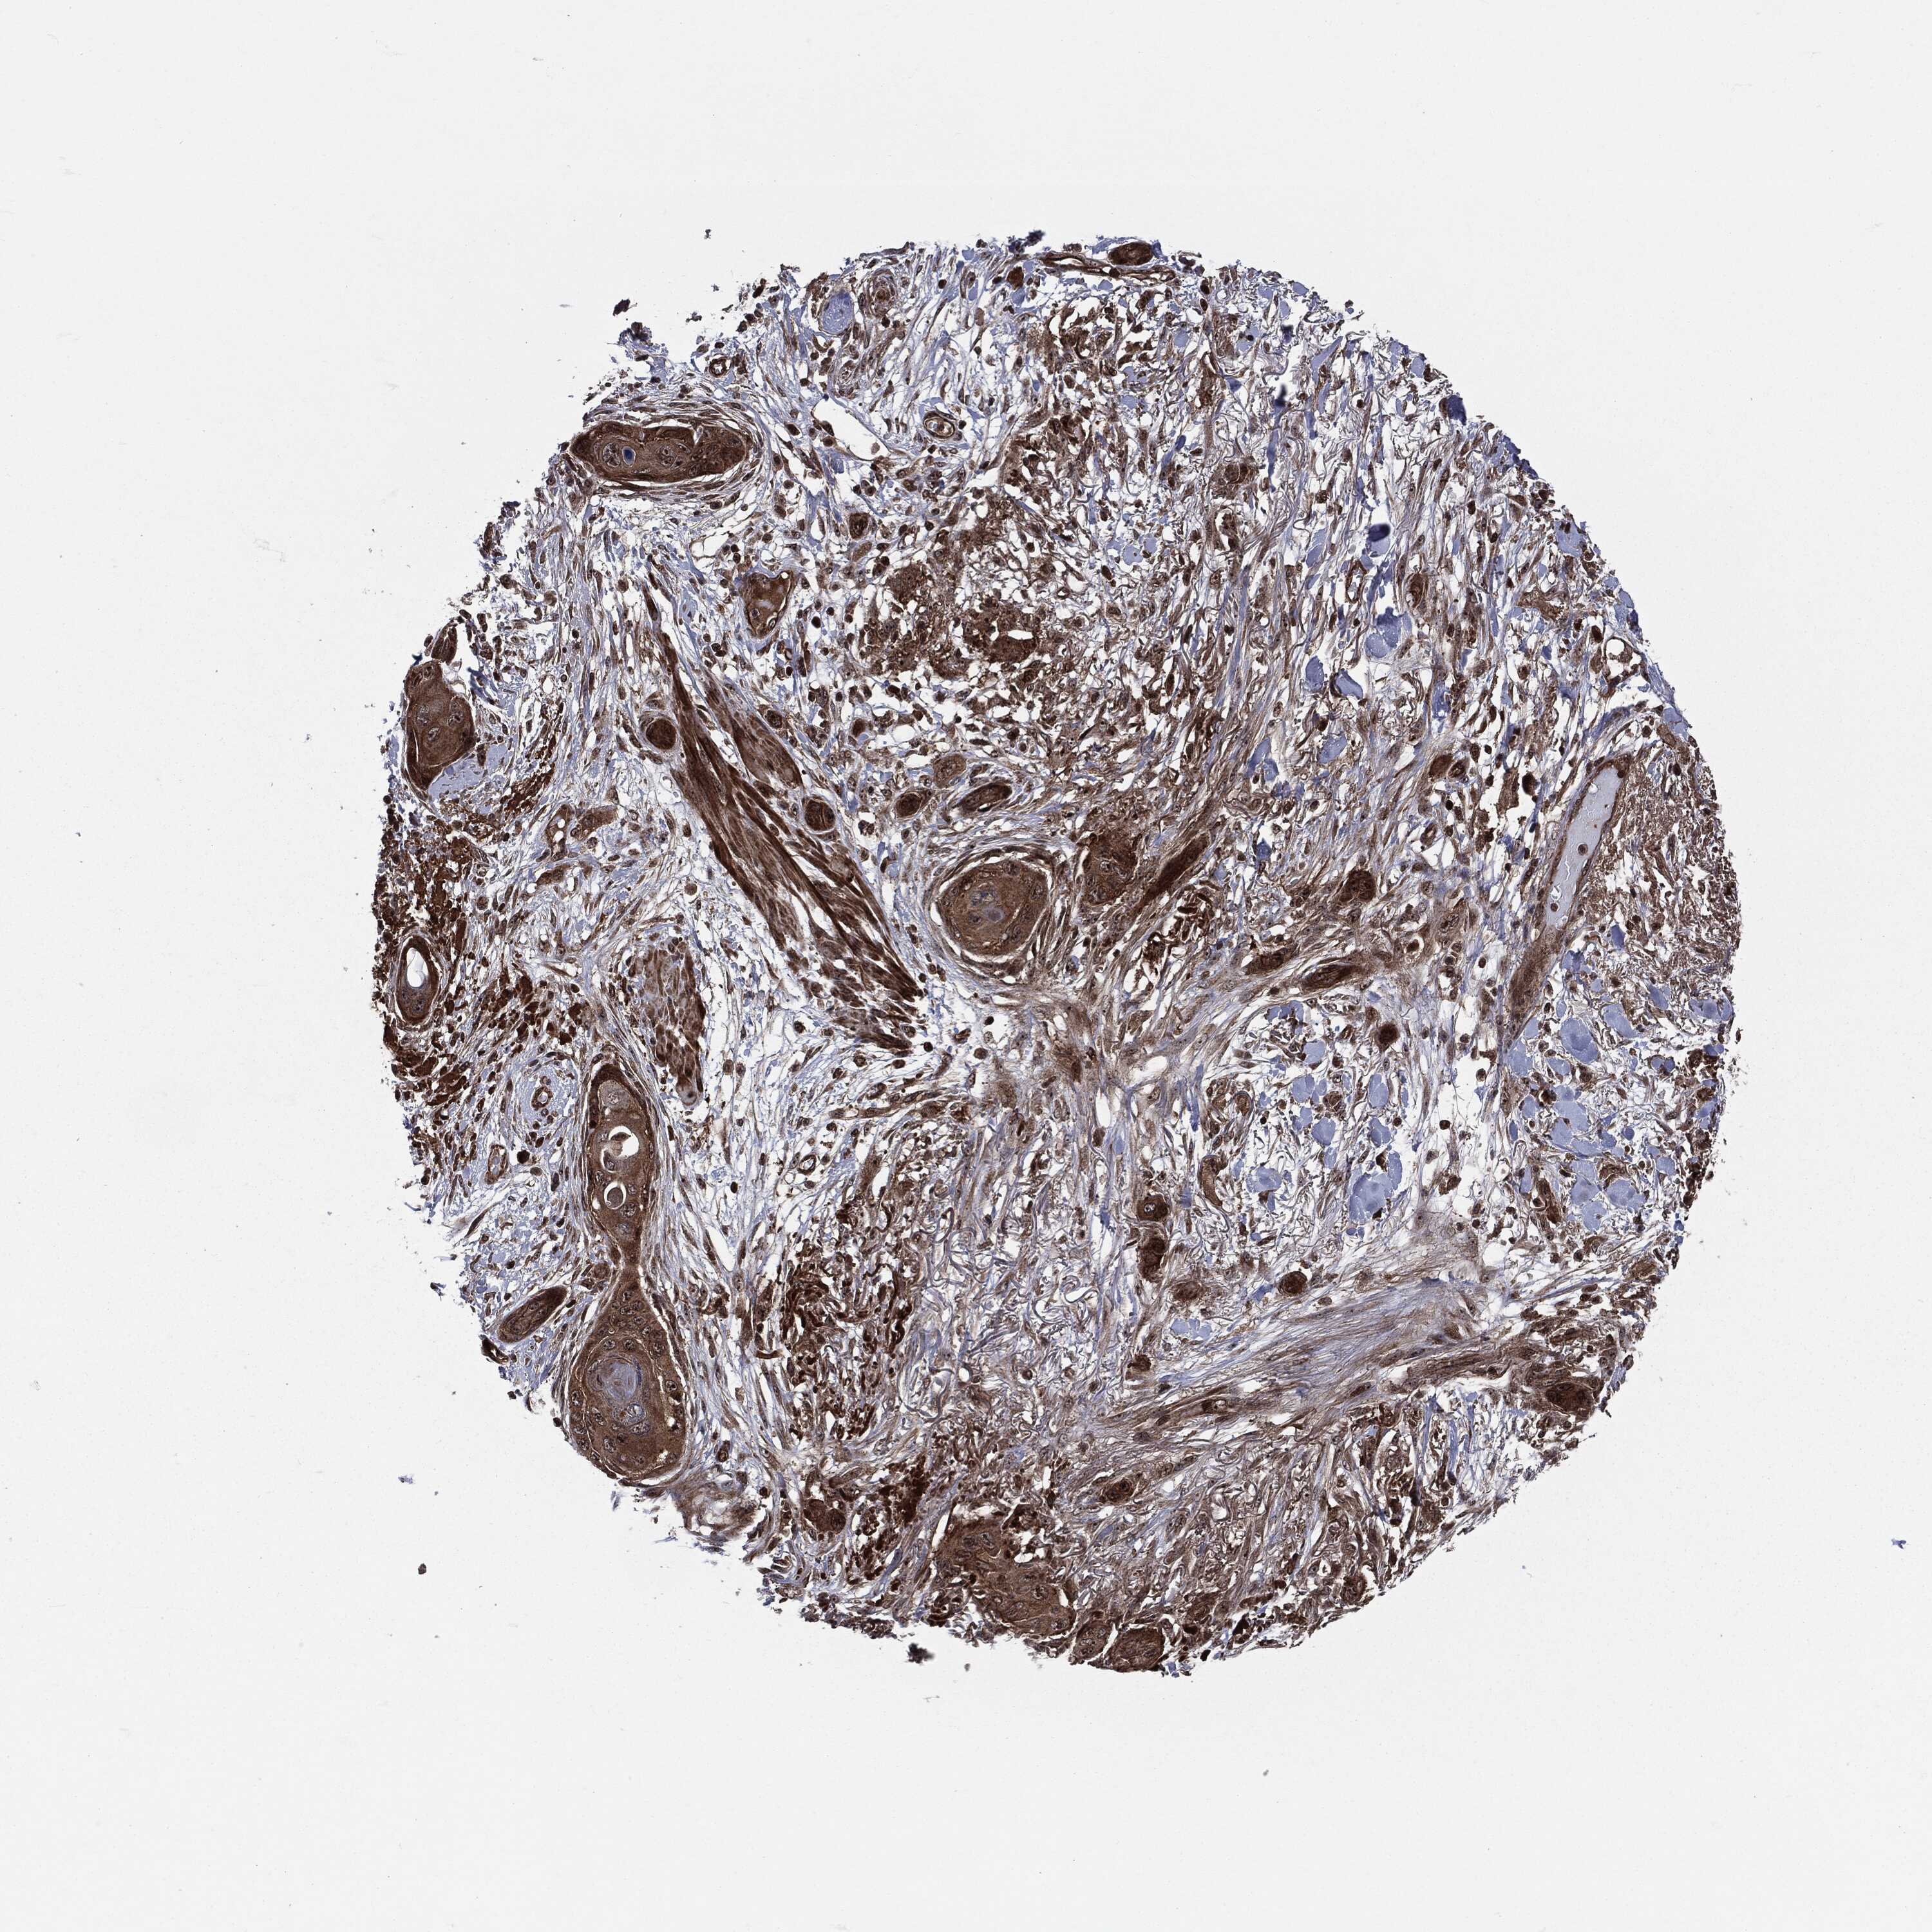

SKIN CANCER - Protein expressioni

A mouse-over function shows sample information and annotation data. Click on an image to view it in a full screen mode. Samples can be filtered based on level of antibody staining by selecting one or several of the following categories: high, medium, low and not detected. The assay and annotation is described here.

Antibody stainingi

Antibody staining in the annotated cell types in the current human tissue is reported as not detected, low, medium, or high, based on conventional immunohistochemistry profiling in selected tissues. This score is based on the combination of the staining intensity and fraction of stained cells.

Each image is clickable and will lead to virtual microscopy that enables deeper exploration of all samples and also displays staining intensity scores, fraction scores and subcellular localization as well as patient and tissue information for each sample.

Antibody HPA041933

Staining

High

Intensity

Strong

Quantity

>75%

Location

Nuclear

Basal cell carcinoma

Squamous cell carcinoma, NOS